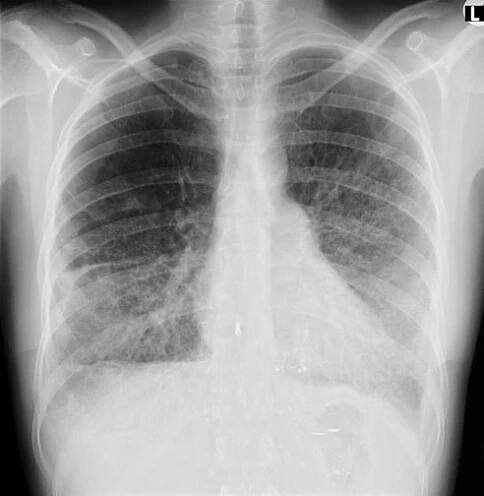

Na CT plic se zobrazil nález - ložisko S 10 L plíce vel až 10 cm. Po přečtení snímků plicním odborným lékařem, byla potvrzena výrazná arterie odstupující z hrudní aorty směrem k centru ložiska ( jde o cystu s tekutinou), byl vyvrácen…